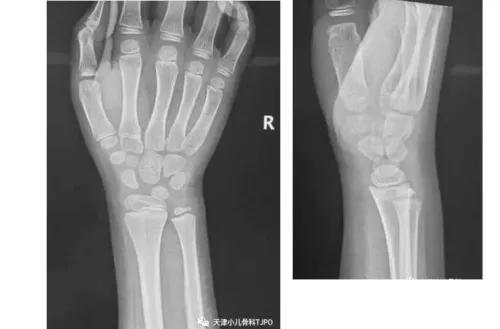

9岁,男,不慎摔倒右腕无明显肿胀,轻压痛外旋明显;X线未见明显骨折。